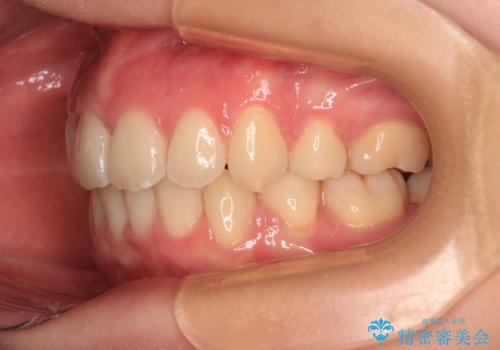

口の閉じにくさが改善され、横顔のシルエットも大幅に改善されました。